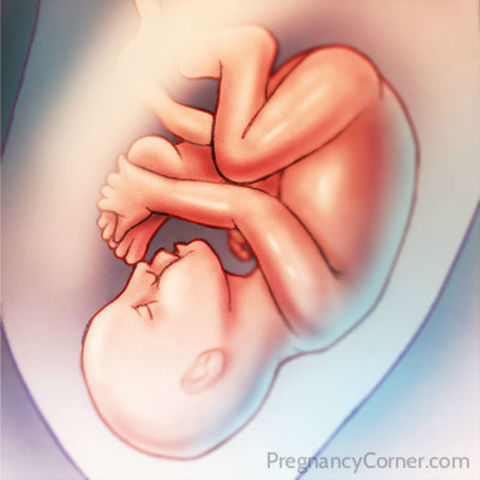

• Week Twenty-Eight Progression

Week Twenty-Eight Progression

The baby's milk teeth have developed under their gums and the hair on their head is clearly seen. The baby has a regular schedulenow, for instance what times they are active or asleep.

• Week Twenty-Nine Progression

Week Twenty-Nine Progression

The baby now wieghs abut 1150 gm. They are able to respond to pain and their muscles and lungs continue to mature. The baby is sensitive to light and begin to develop taste preferences.